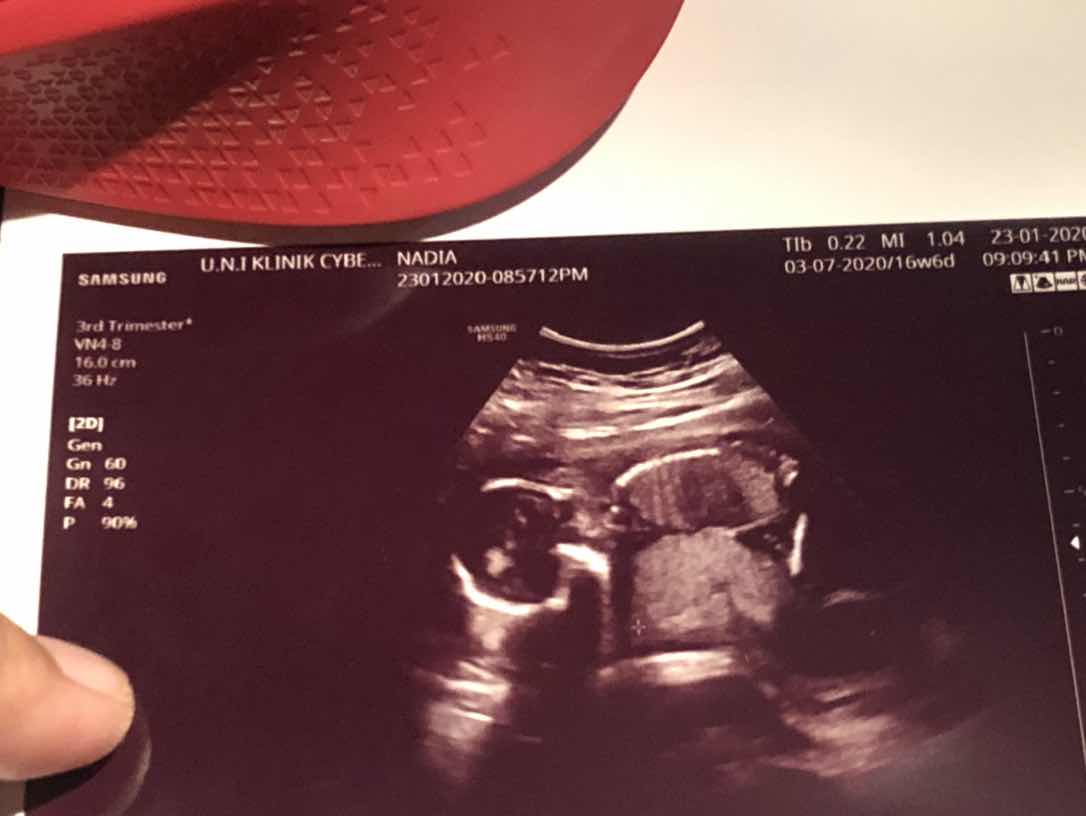

Scan gender - 17weeks

Hi mommies, just nak share..tadi saya scan baby in hoping dapat tahu gender..mula2 doc scan tu, baby dah tunjuk kemaluan dia ? terpampang bentuk hamburger, tapi doc tak berani nak jamin 100%.. Ada tak mommies kat sini mula2 scan nampak macam baby girl, tapi lama2 bila besar nampak boy? Ingat nak slow2 beli barang baby, tapi x berani lagi beli yg pinky2 punya